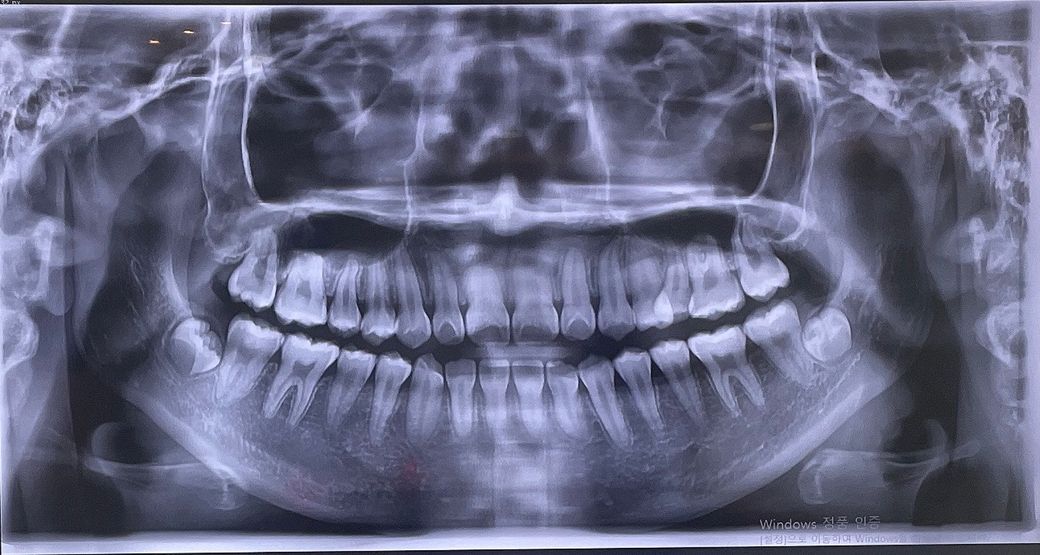

이렇게 봤을때 턱관절에 문제가 있는건가요?

턱에서 딱딱 소리가 났다 안났다 그러고 불편감이 있어서

엑스레이를 찍어보긴 했는데 봤을때 이게 턱관절에 문제가 있는건가요 아님 별 다른 문제는 없는건가요?

엑스레이 측면사진도 있으면 좋겠네요 정면사진상으로 이상은 없는것 같습니다 교근이라는근육의 과긴장으로 턱관절에서 소리가 날수도 있습니다

X-레이 사진만으로 턱관절 장애를 완전히 진단하기는 어렵습니다. X-레이에서 명확한 이상이 보이지 않더라도, 연조직 문제나 초기 단계의 장애일 수 있습니다. 추가적인 검사(CT, MRI 등)를 진행할 수 있을 것 같습니다.